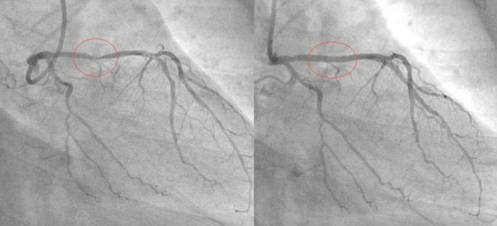

这位Hakim让他自己在家中做一个食疗,他吃了一个月。一个月后他去同一家医院做检查,发现三条血管干干净净,原来堵塞的地方已经全通了。他是一位虔诚的回教徒,为了让更多的人受益,他把自己的经验放在网上分享,他的前后两张血管照片也放了在网上,在 照片中,服用食疗之前与之后的分别连普通人也看得出来。